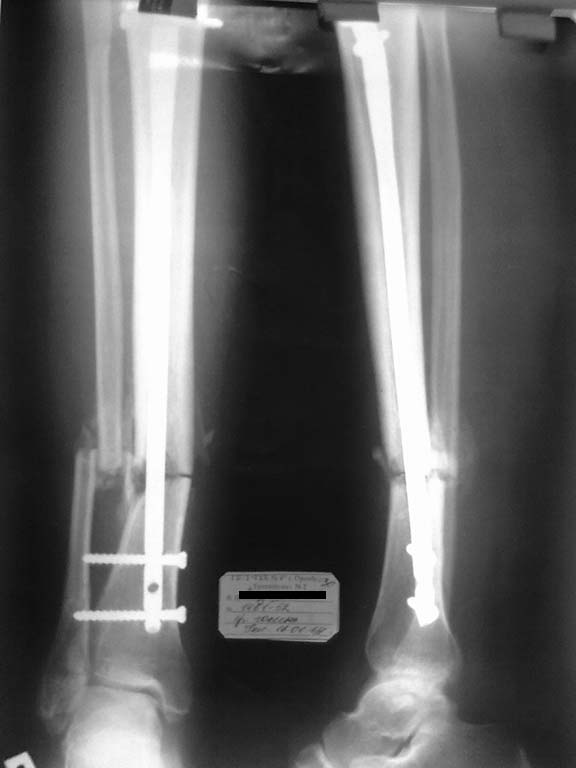

Спасибо большое за советы, но получилось "по-нашенски" - послушал-послушал и сделал по-своему:

1. разобщить отломки м/берцовой кости не удалось - полная консолидация, после остотомии м/берцовой кости в обл. перелома подвижности особой не добились - причина видимо в синостозировании берцовых костей, произвели резекцию, выбрал 2,5см(однако при исправлении оси дефект оказался больше -этого не учел()

2. Пробовал, после резекции м/берцовой кости макс. приводить дист. отломок под ЭОП-контролем, ось исправлялась не до конца, мешала образовавшаяся(все-таки 3 мес.)мозоль, после клиновидной остеотомии (хотя клин оч. узкий брал 3-4мм.) появилась возможность исправить вальгус

3.Поставил 4 позиционных спицы, а вот реконструктивный штифт взять возможности не было, блокировать в динамике после таких манипуляций было страшновато ( да и все-таки это не псевдоартроз), блокировал в статике, продинамизирую - не поленюсь).

Снимки представляю, считаю получилось приемлемо.